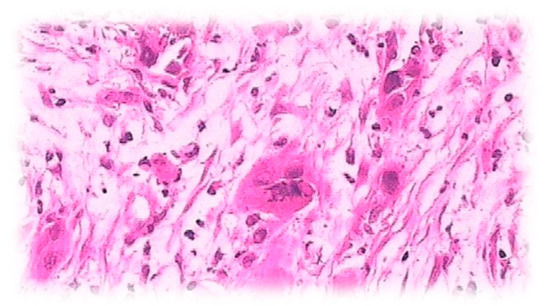

2. Results

3. Discussion